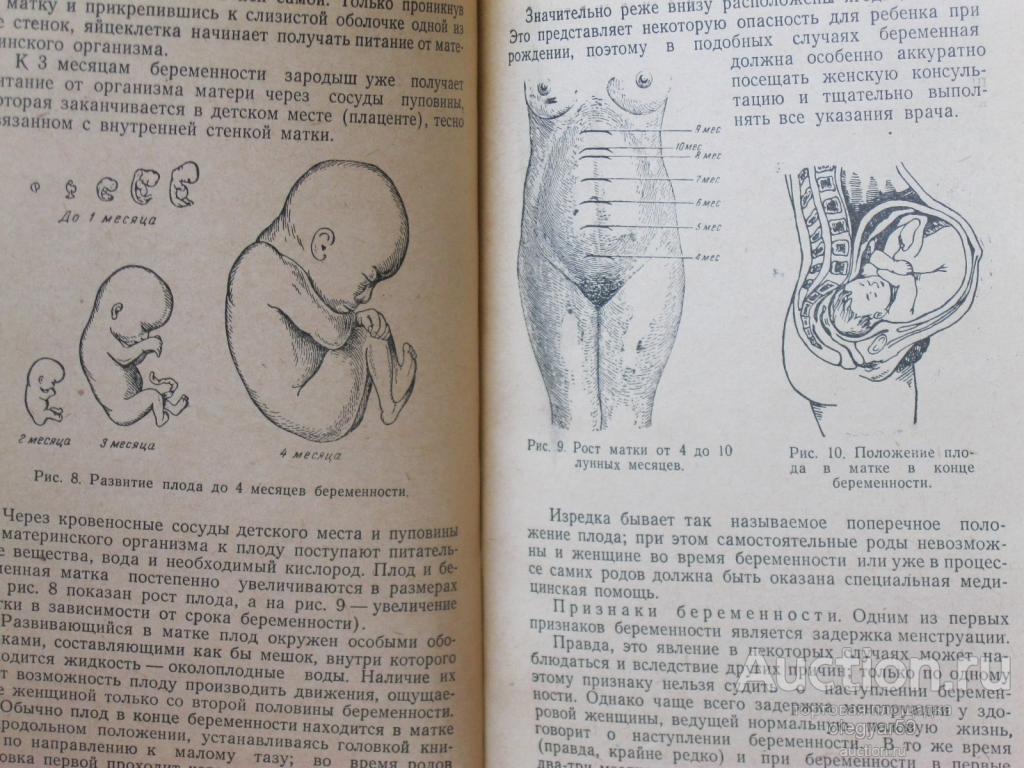

Расположение плода на 15-й неделе беременности: фотографии и иллюстрации